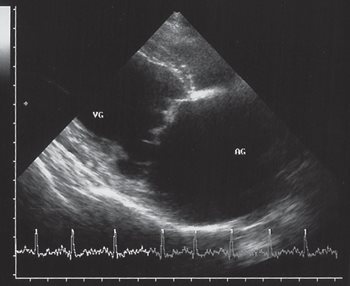

Right lateral (figure 1) and dorso-ventral (figure 2) thoracic radiographs revealed bilateral cardiomegaly (Buchanan’s vertebral scale = 13 ; normal = 9.7 +/- 0.5 [5] ; the transverse diameter was more than 2/3 of the total diameter of the thorax).

Figure 1: right lateral thoracic radiograph: left-sided cardiomegaly, venous densification, and alveolar pulmonary oedema.

The size of the left atrium was particularly increased. The tracheo- vertebral angle was decreased. Pulmonary venous densities were present on the lateral view (figure 1). The pulmonary parenchyma showed interstitial and alveolar densities consistent with alveolar pulmonary oedema (figures 1 and 2).

These radiographs confirmed the diagnosis of congestive disease with pulmonary oedema.